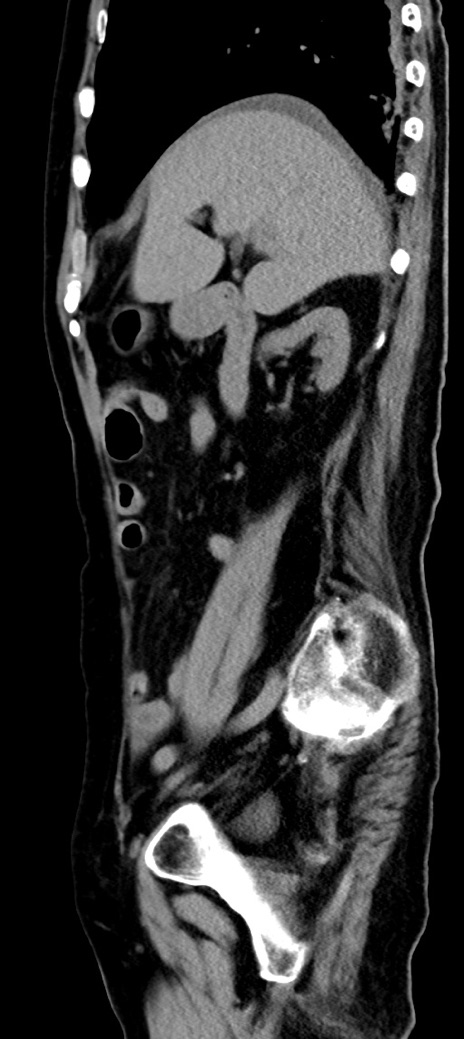

横断像

他院CT